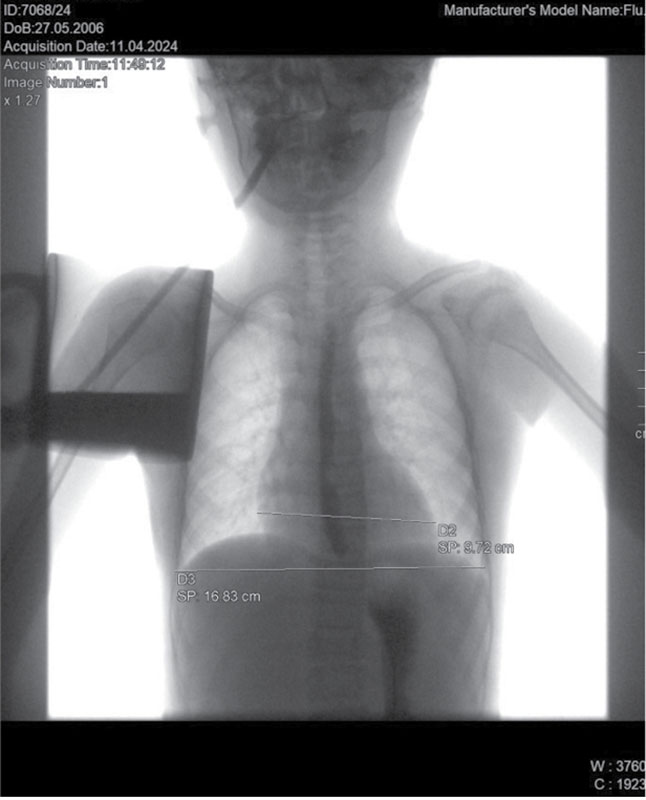

Рис. 2. Рентгенологическое исследование органов грудной клетки. Сердечно-грудной индекс – 0,57 (горизонтальный размер тени сердца – 9,72 см)

Рентген органов грудной клетки: отмечается повышенный горизонтальный размер тени сердца, однако в динамике отмечается снижение до 9,72 см. Сердечно-грудной индекс также снизился до 0,57 (рис. 2).